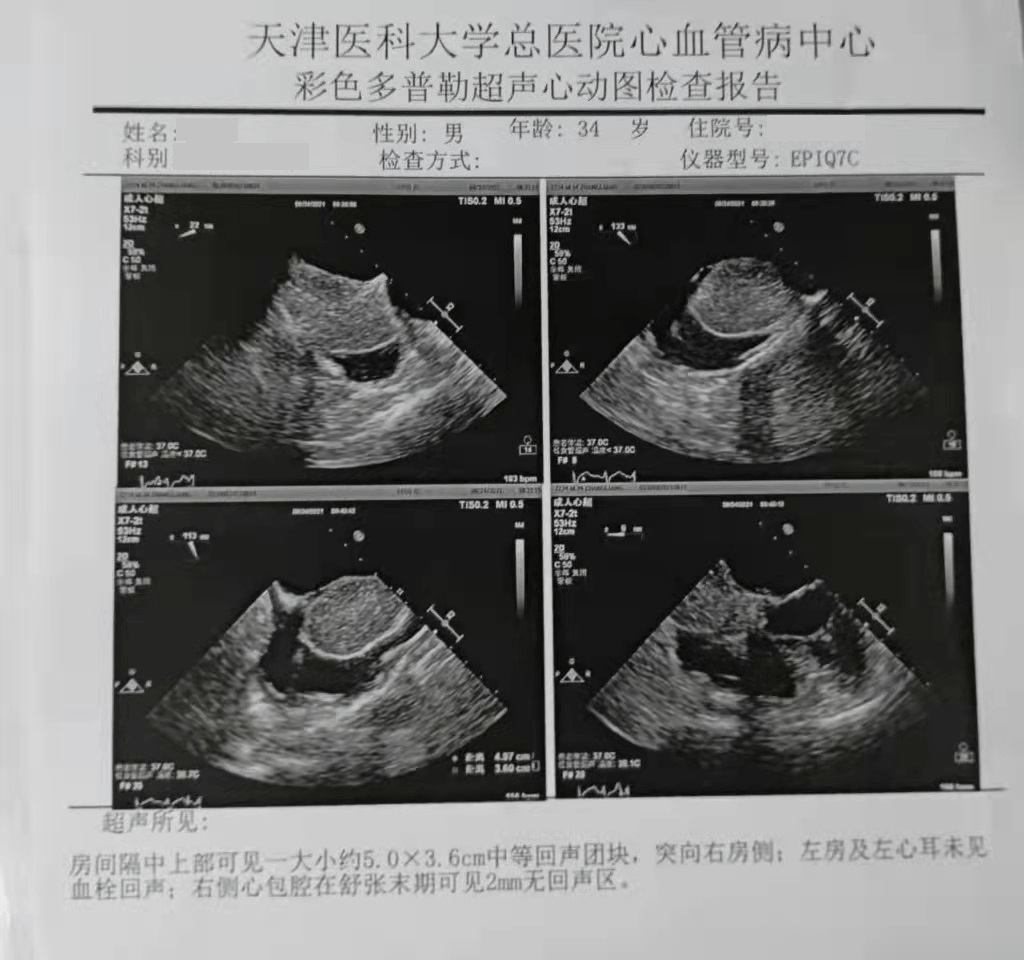

(超声提示 , 患者心房间隔可探及一大小约4.5*3.6cm大小中等回声团块 , 各瓣膜结构未见明确异常)

(超声提示 , 房间隔中上部可见一大小约5.0*3.6cm中等回声团块 , 凸向右房侧)